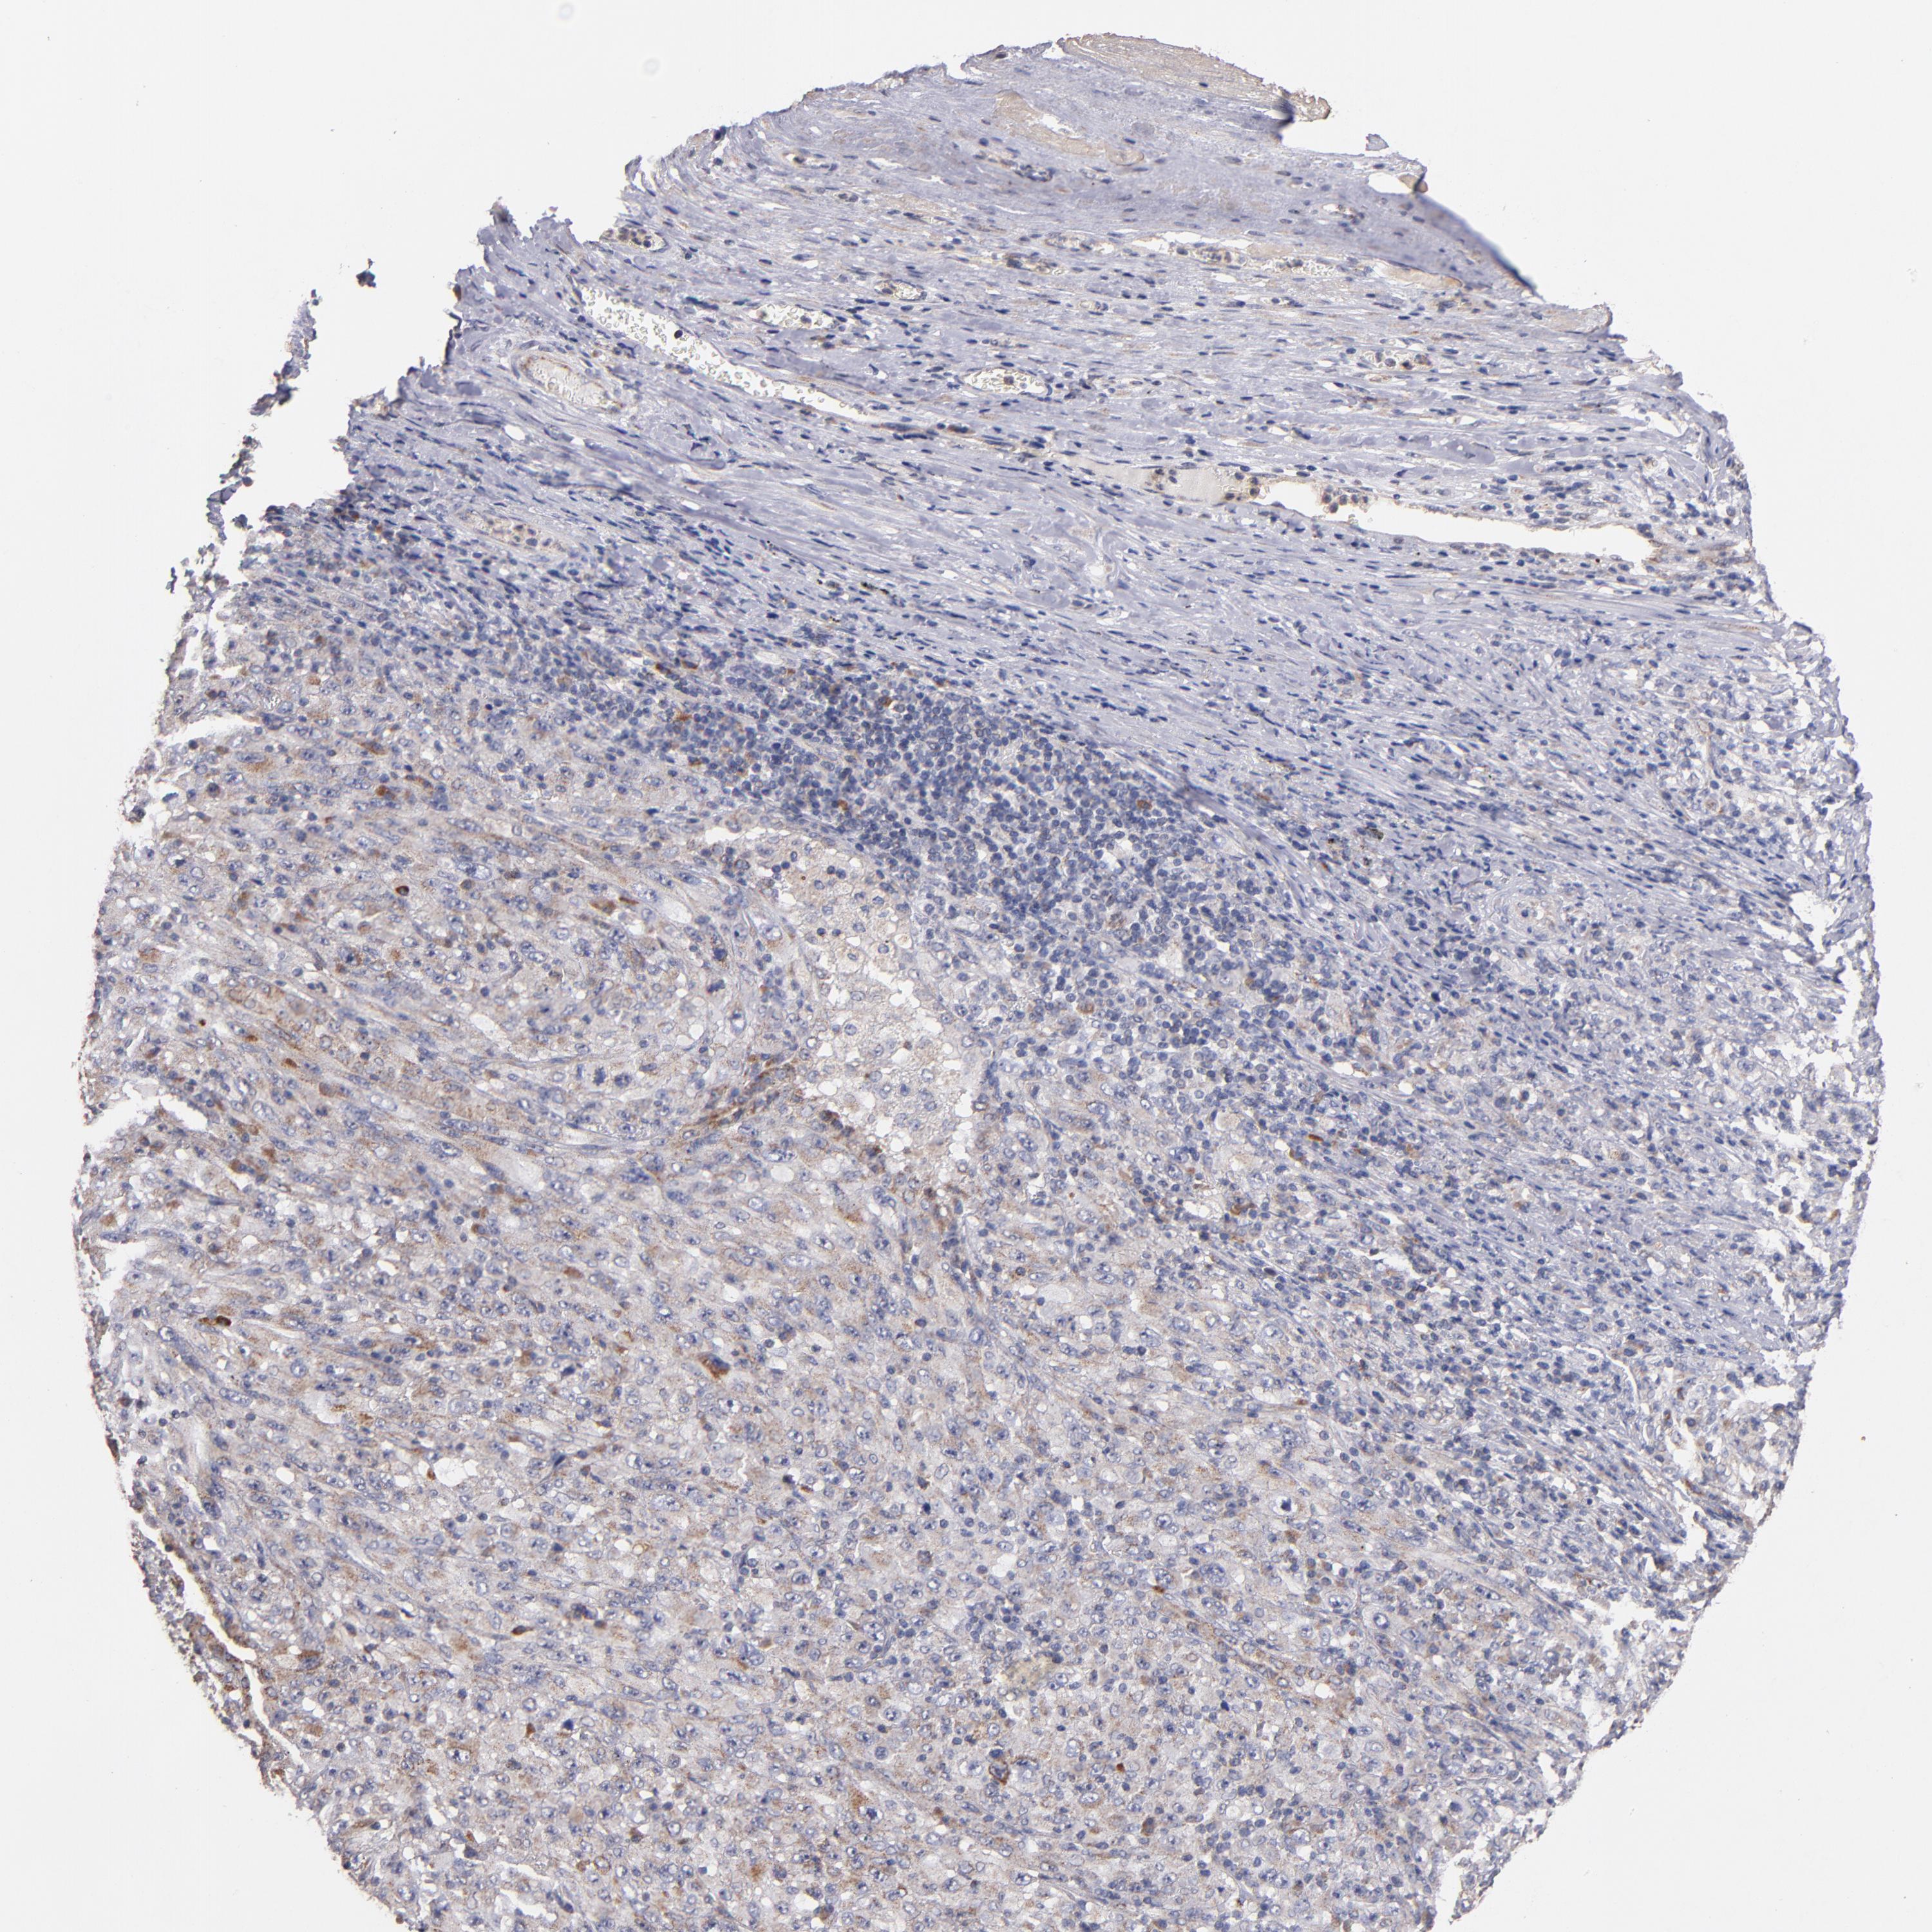

MELANOMA - Protein expressioni

A mouse-over function shows sample information and annotation data. Click on an image to view it in a full screen mode. Samples can be filtered based on level of antibody staining by selecting one or several of the following categories: high, medium, low and not detected. The assay and annotation is described here.

Note that samples used for immunohistochemistry by the Human Protein Atlas do not correspond to samples in the TCGA dataset.

Antibody stainingi

Antibody staining in the annotated cell types in the current human tissue is reported as not detected, low, medium, or high, based on conventional immunohistochemistry profiling in selected tissues. This score is based on the combination of the staining intensity and fraction of stained cells.

Each image is clickable and will lead to virtual microscopy that enables deeper exploration of all samples and also displays staining intensity scores, fraction scores and subcellular localization as well as patient and tissue information for each sample.

Antibody HPA001825

Antibody CAB003857

Staining

High

Medium

Low

Not detected

Intensity

Strong

Moderate

Weak

Negative

Quantity

>75%

75%-25%

<25%

None

Location

Nuclear

Cytoplasmic/membranous

Cytoplasmic/membranous,nuclear

Malignant melanoma, NOS

Malignant melanoma, Metastatic site